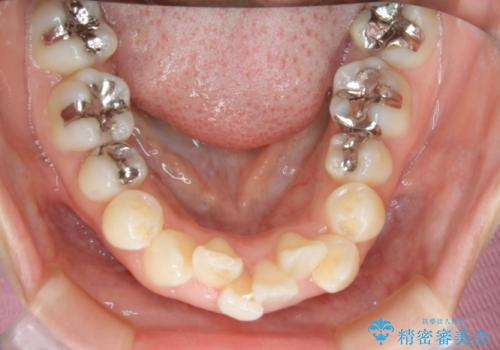

- 歯のガタつきと出っ歯が気になるので矯正治療を希望し来院された患者様です。

上下顎とも歯を並べられるスペースが無く、口元を下げたいというご希望だったので、抜歯とワイヤー矯正を併用した治療を計画しました。

抜歯スペースを利用し口元を大きく下げることが出来ました。